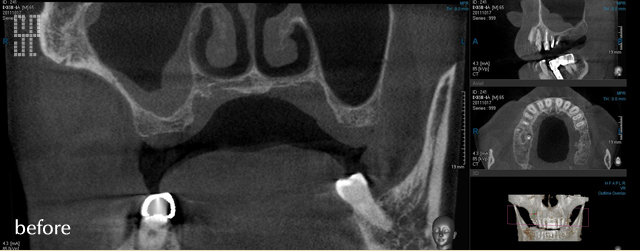

インプラントの構造は図のように、上部構造・アバットメント・インプラント体(人工歯根)の大きく3つの部位に分けられます。

歯を失った骨にインプラント(人工歯根)を埋め込み、その上に歯を立ち上げます。 歯の欠損が与える影響は、機能・審美・そして精神的にも大きなダメージです。インプラントは、歯の欠損における有効な治療法なのです。